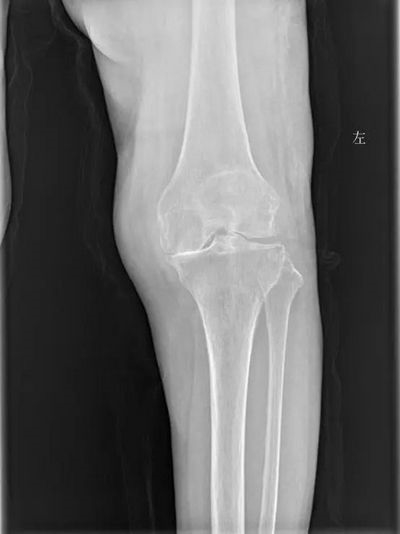

徐明杰主任仔细询问了病史,做了查体,并查看了影像学检查,指出患者目前为重度膝骨关节炎,K-L分期为3期,患者保守治疗效果差,对生活质量的影响明显,在这个时期,可以考虑行膝关节置换。王奶奶办了住院后,管床医师张鹏飞立刻完善相关检查,徐明杰主任为患者做好术前规划,考虑患者左侧髋关节已行水泥型人工股骨头置换术,术前规划时徐明杰主任特意联系厂家备股骨端的短杆定位器,入院第3天行左侧膝关节双间室置换术。手术采用髌前入路,术中股骨定位、截骨按照术前规划完成,手术操作期间注意间隙平衡、软组织平衡,顺利完成。

术前检查